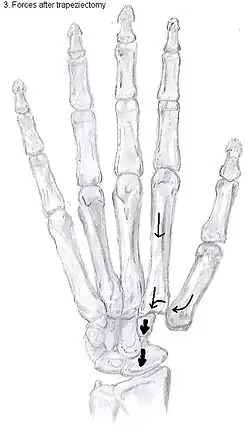

Trapeziectomy

During trapeziectomy,[30] the trapezium bone is removed without any further surgical adjustments. The trapezium bone is removed through an approximately three centimeter long incision along the lateral side of the thumb. To preserve surrounding structures, the trapezium bone is removed "by splitting" it into pieces.

An empty gap is left by the trapeziectomy and the wound is closed with sutures. Despite this gap, no significant changes in function of the thumb are reported.[27] After the surgery, the thumb will be immobilized with a cast.

Trapeziectomy with tendon interposition

Some physicians still believe that it is better to fill the gap left by the trapeziectomy. They assume that filling the gap with a part of a tendon is preferable in terms of function, stability and position of the thumb. This is based on the assumption that interposition can help maintain the space between the metacarpal and the scaphoid, which will improve comfort and capability. Neither of these assumptions is supported by experimental evidence.

Trapeziectomy with ligament reconstruction

Another technique is used to reconstruct the volar beak ligament after trapeziectomy. The rationale is that ligament reconstruction(LR) helps maintain the gap between the metacarpal and the scaphoid, and that a larger gap is associated with greater comfort and capability.[32] Again these possibilities are not supported by experimental evidence.

Trapeziectomy with LRTI

Some physicians believe that combining LR with TI will help maintain gap between the metacarpal and the scaphoid.[33] And that doing so will improve comfort and capability. Keep in mind that these aspects of the rationale are not supported by experimental evidence. The evidence suggests that all of these procedures have comparable long-term results.

Arthrodesis

Arthrodesis of the TMC joint is a surgical procedure in which the trapezium bone and the metacarpal bone of the thumb are secured together. They are held together by K-wires or a plate and screws until the bone will heal.

Disadvantages include inability to flatten the hand.[27] Additionally, the stress on the CMC joint is now spread over the adjacent joints, those joints are more likely to develop osteoarthritis.[34]